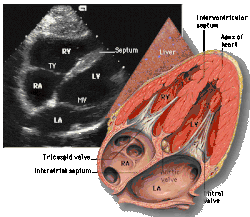

![]() Subcostal four chamber | ![]() Apical four chamber | ![]() Parasternal long axis | ![]() Parasternal short axis | ||||||||

| Each figure contains a TTE with a black background, and a corresponding colored illustration. | Patrick J. Lynch and C. Carl Jaffe, Yale University, 2006. | ||||||||||

| Click on a figure to enlarge it and see some parts of the heart identified. RV, right ventricle; LV, left ventricle; RA, right atrium; LA, left atrium; TV, tricuspid valve; MV, mitral valve; AV, aortic valve; RVOT, right ventricular outflow tract; LVOT, left ventricular outflow tract | |||||||||||